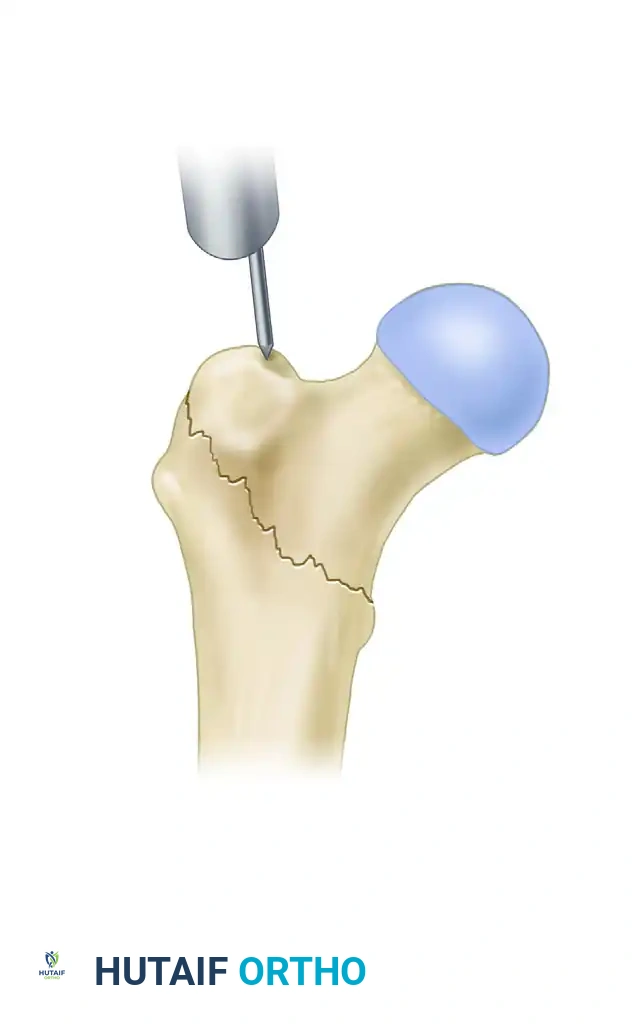

For the fixation of intertrochanteric femoral fractures, the selection of the entry portal is arguably the most critical step of the operation. We advocate for the modified medial trochanteric portal.

Anatomical Landmarks: The modified medial trochanteric portal is located on the medial aspect of the greater trochanter, directly along the trochanteric ridge on the AP view, and perfectly in line with the central axis of the femoral shaft on the lateral view.

💡 CLINICAL PEARL: In a landmark cadaveric study, Perez et al. demonstrated that utilizing this slightly medialized portal avoids damage to the gluteus medius tendon insertion. This significantly reduces postoperative abductor weakness and the incidence of a persistent Trendelenburg gait compared to the traditional tip-of-trochanter portal.

2. Incision and Guide Pin Placement

- Make an approximately 3-cm longitudinal incision, beginning 3 cm proximal to the tip of the greater trochanter and extending proximally. (Note: This incision may need to be extended in morbidly obese patients).

- Sharply incise the fascia lata and the aponeurosis of the gluteus maximus in line with the skin incision. Bluntly split the abductor muscle fibers to palpate the trochanteric tip.

- Localize the entry point with a guide pin on the medial aspect of the greater trochanter.